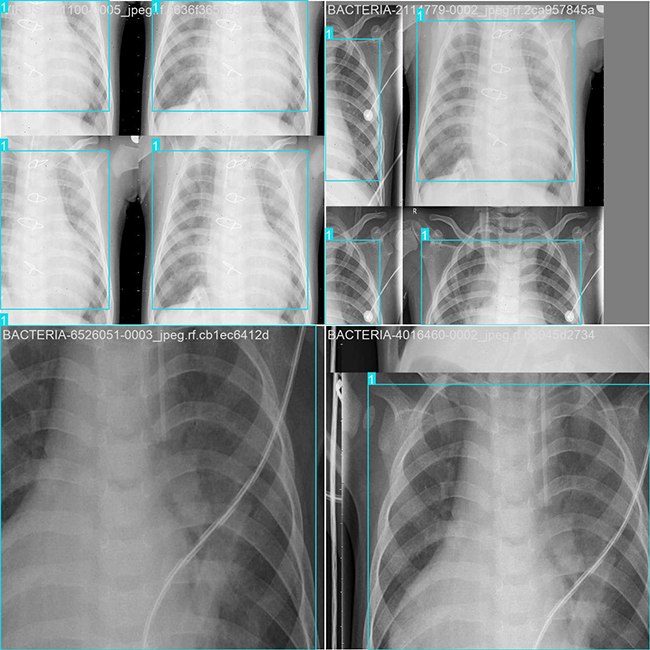

部分数据集图像如下图所示:

部分标注如下图所示:

这种数据分布方式确保了数据在模型训练、验证和测试阶段的均衡性,并为其开发及性能评估提供了坚实的保障